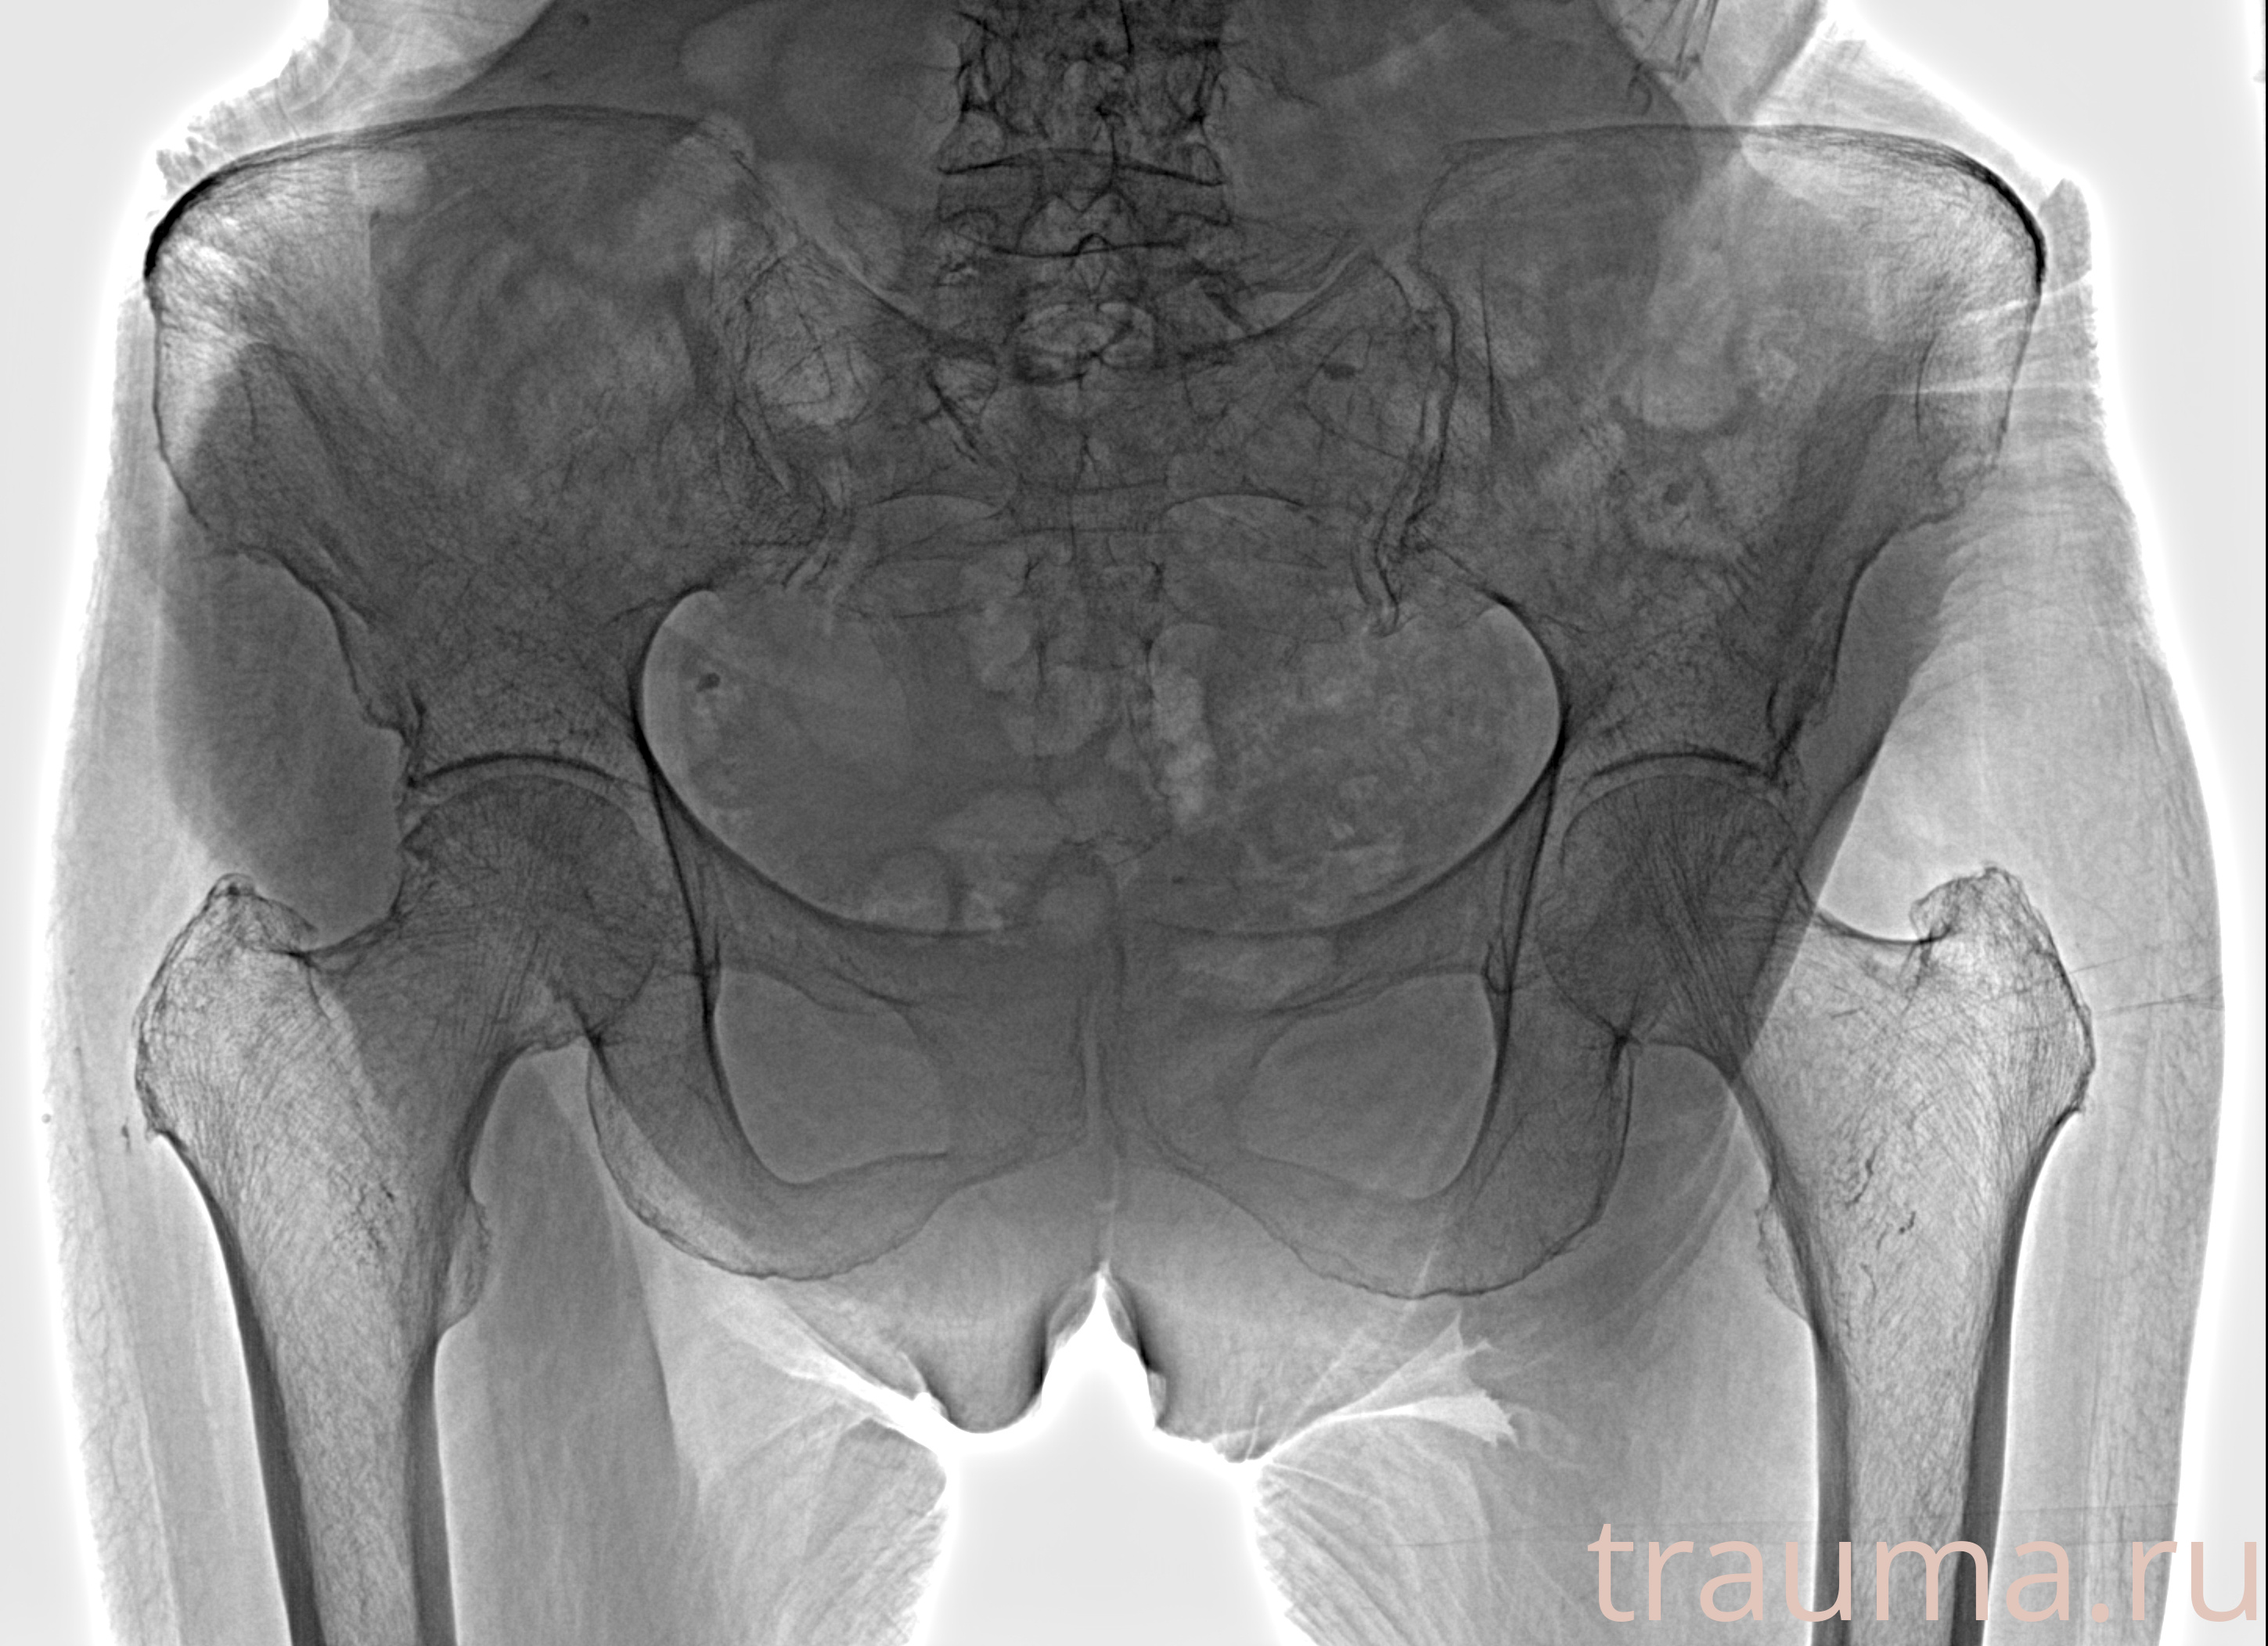

Рентгенограммы

Рентген на дому: по вашему адресу приезжает врач-рентгенолог, травматолог-ортопед с мобильным рентгеновским аппаратом, проводит диагностику травмы или заболевания, делает необходимые рентгенограммы, дает рекомендации по дальнейшему лечению. Получить качественные снимки в домашних условиях возможно благодаря уникальной методике, разработанной МосРентген Центром для института  Склифосовского